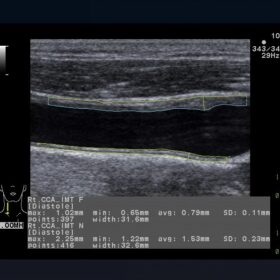

Cardiovascular

- eTRACKING (Echo Tracking)

- Arterial Stiffness

- Flow Mediated Dilatation (FMD)

- Wave Intensity (WI)

- Automated Intima-media Thickness (IMT) Measurement